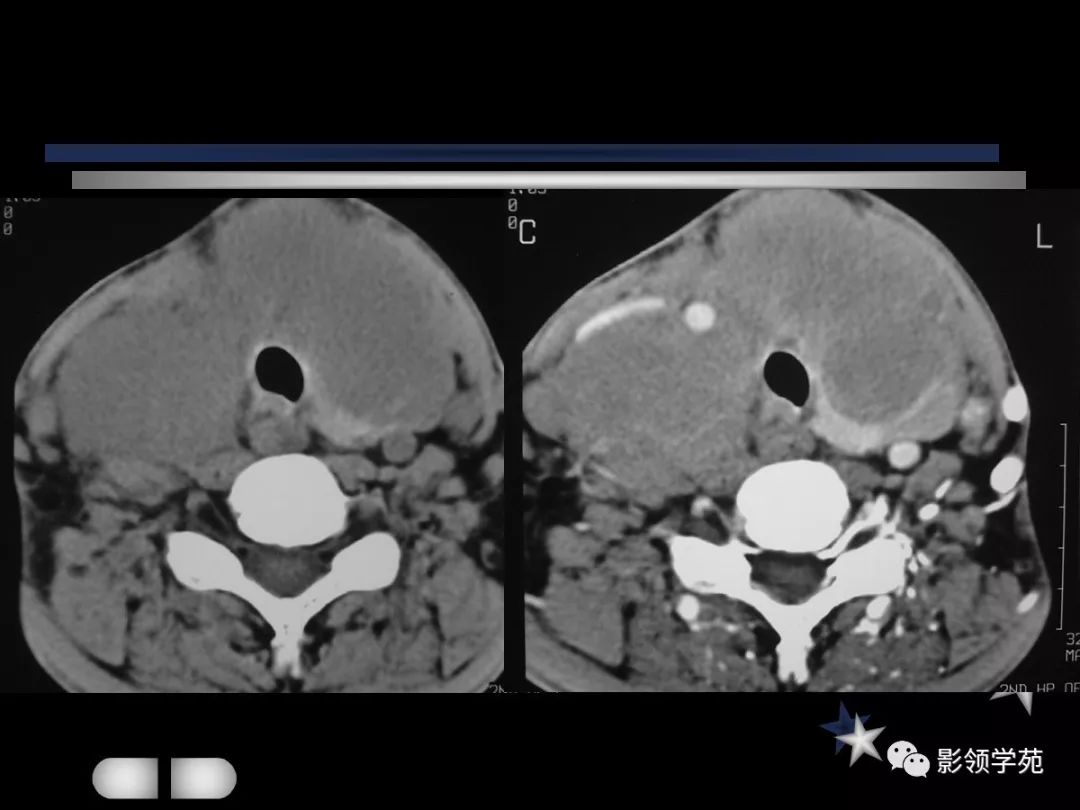

- MRI上实性肿块在T1WI上呈等低信号,在T2WI上呈高信号,囊变区呈长T1长T2信号,钙化在T1WI及T2WI上均呈低信号。

- 甲癌晚期肿瘤常突破甲状腺被膜向周围侵润

- 在增扫时可见环状强化。

- 由于CT和MRI能增强扫描可以清晰显示甲癌的侵润范围和程度,以及显示淋巴结的转移情况

- 手术前分期,指导治疗计划